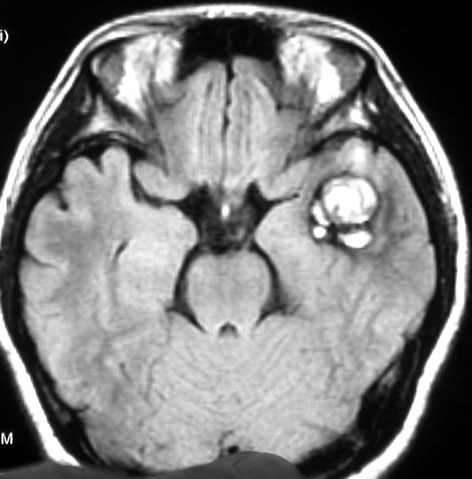

腫瘍から少し出血したために,患者さんはけいれん(てんかん発作)を起こしました。左のT1強調画像では出血を疑います。中央のT2強調画像では海綿状血管腫の周りに脳浮腫があるために白くぼやけた部分があります。右の造影剤を使ったMRIでは造影剤が入るところがほどんど無いことがわかります。側頭葉の海綿状血管腫は側頭葉てんかんという症状で発症することが多いです。

出血が溶けて少し小さくなっています。海綿状血管腫の周りには黒い縁取りがあります。この黒い部分は血液が溶けて残った鉄が脳の中にたまったことを示しています(siderosisといいます)。この鉄のしみ込みはけいれんの原因になると考えられます。この海綿状血管腫は中等度の大きさですが,治療が難しいほどのてんかんが無ければ手術などしないでほっておいてもいいです。手術で側頭葉(特に海馬)を損傷すると記憶の障害などもでます。